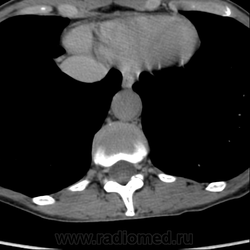

Выкладываю по очереди срезы на одинаковых уровнях, сначала паренхиматозная, потом отсроченная фазы.

вот на этой картинке никто ничего подозрительного не заметил???

или я придираюсь или там что-то под правой почкой есть!!! сканограм побольше бы?!!!! можно еще немного кадров корон в венозную фазу выложить????

Не придираетесь, однозначно что-то есть. Что - не знаю, на днях посмотрю серию и если что выложу